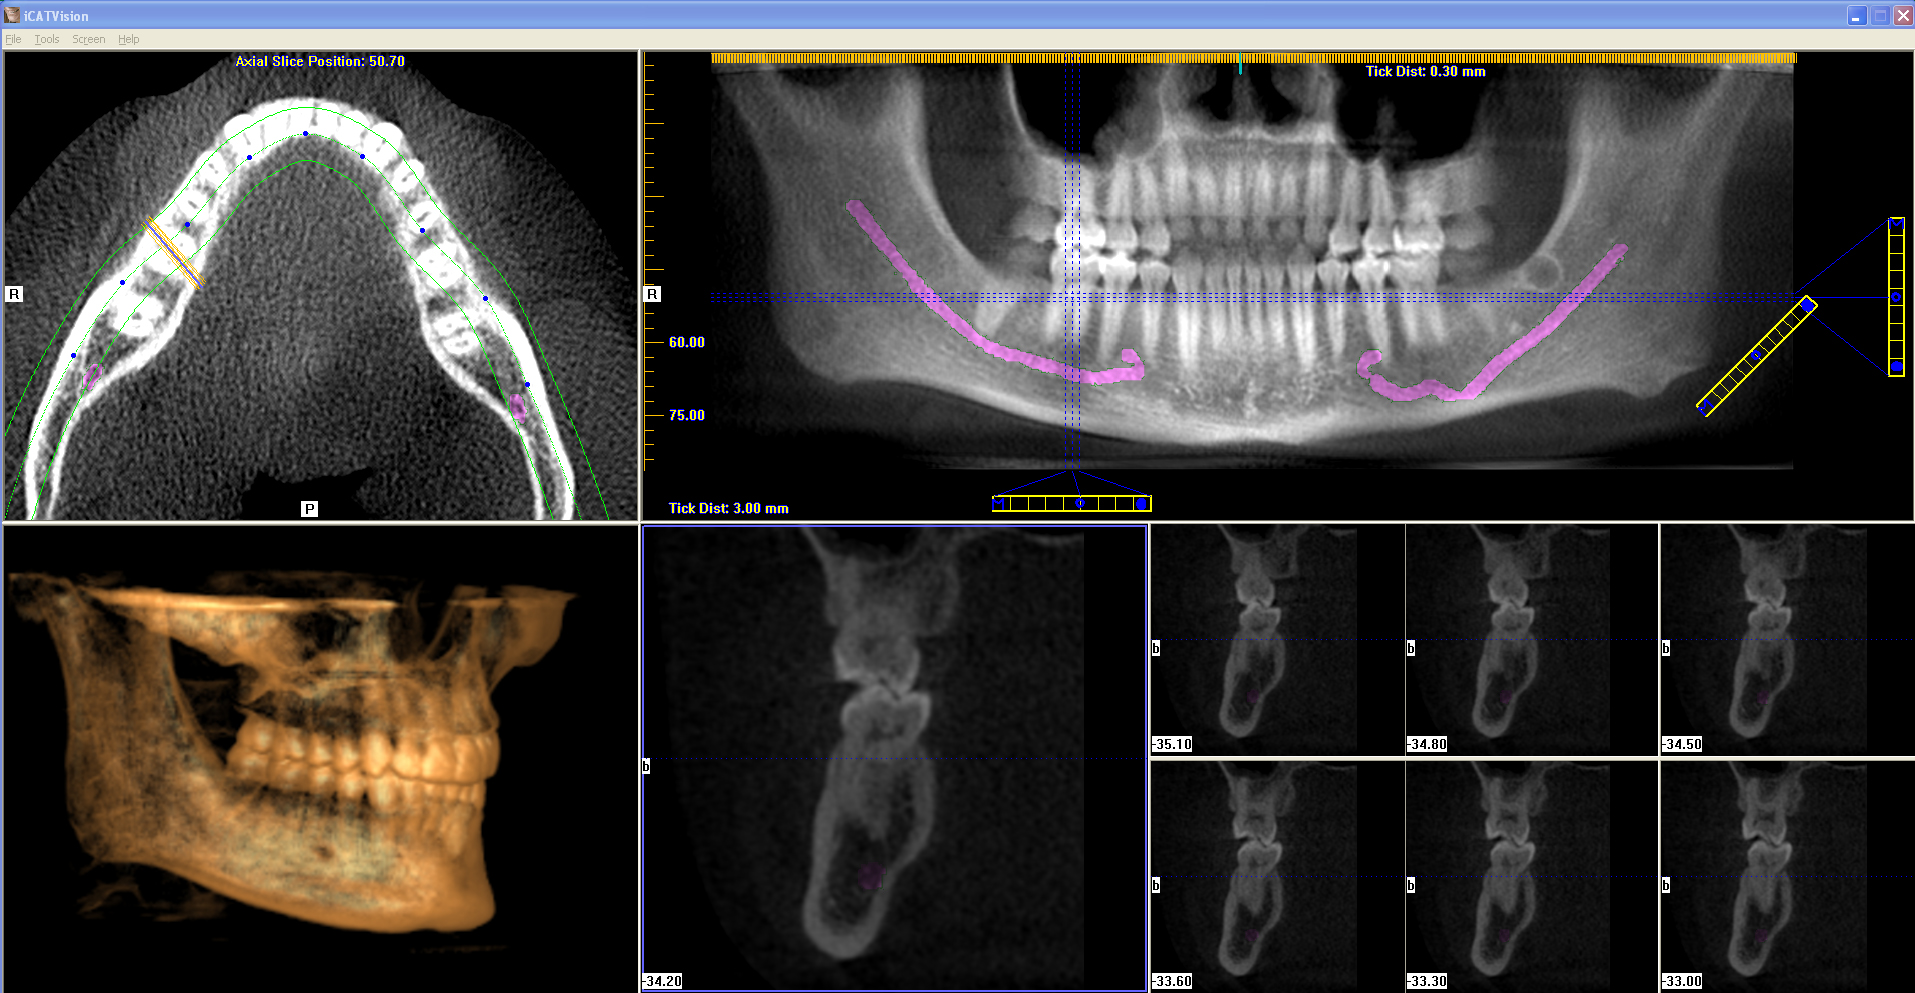

Dental Implant Imaging in Eatontown, NJ Dr. Marc E. Gordon

Dental Scan For Implants Allow your dentist to plan your implant. Dentists use cbct scans as a diagnostic tool to make implant treatment as accurate as possible. If you have missing teeth and are interested in dental implants, chances are you’ve been told you must have a cbct scan to progress with your treatment. Allow your dentist to plan your implant. This is where dental ct scans come in. Pic dental provides the winning full arch implants solution consisting of the pic system, the world’s first and most precise implants oral scanner for taking digital impressions of multiple dental implants and pic. The scans will allow the dentist to determine bone quantity and. Clinical evaluation and radiographic analysis of the bone must be carried out for every patient before the dentist can move on to implant planning. These scans also serve as a powerful tool for determining whether you are a suitable candidate for dental implants in the first place. Ideally an implant site has at least 7 mm of. This is why a ct scan of the jaw bone, which. This type of ct scan uses a cone.

From www.drmgordon.com

Dental Implant Imaging in Eatontown, NJ Dr. Marc E. Gordon Dental Scan For Implants This type of ct scan uses a cone. These scans also serve as a powerful tool for determining whether you are a suitable candidate for dental implants in the first place. This is where dental ct scans come in. This is why a ct scan of the jaw bone, which. Ideally an implant site has at least 7 mm of.. Dental Scan For Implants.

From www.facialart.com

Why CBCT (Cone Beam CT Scan) is a Must for Patients Receiving Dental Dental Scan For Implants The scans will allow the dentist to determine bone quantity and. This is why a ct scan of the jaw bone, which. This is where dental ct scans come in. Clinical evaluation and radiographic analysis of the bone must be carried out for every patient before the dentist can move on to implant planning. Dentists use cbct scans as a. Dental Scan For Implants.